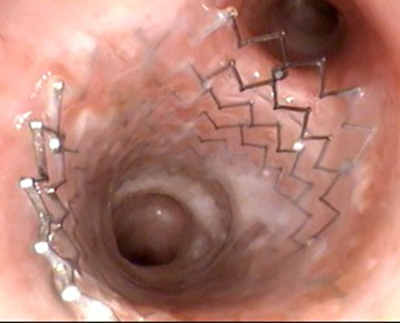

Peytant’s new application for amnion is used in its AMStent Tracheobronchial Covered Stent System (AMStent System). According to its FDA de novo granted marketing authorization, the AMStent System is for use in the treatment of tracheobronchial strictures produced by malignant neoplasms in adult patients. These obstructions are common complications of lung cancers and metastatic tumors. An estimated 25% to 30% of patients with cancers in the lung will have pulmonary obstructions (PO). If untreated, POs can lead to life-threatening respiratory and cardiac failure.

At Peytant’s manufacturing facility in Minnesota, the AM cover is attached to a self-expanding metal stent (SEMS) – an open cell nitinol stent scaffolding – so the stent is encapsulated in AM. The AM-covered stent is loaded onto a traditional over-the-wire deployment catheter for single-use application.